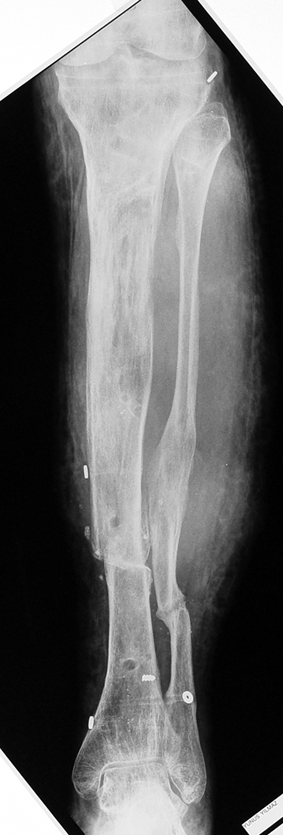

Uygun radikal debridman tüm nekrotik kemik ve yumuşak dokuların çıkartılmasını gerektirir, ve sıklıkla uzuvda instabiliteye neden olur. Kalan kemik ve yumuşak doku defektinin bir şekilde fiksasyonu ve rekonstrüksiyonu gereklidir. İlizarov’un ortaya koyduğu distraksiyon osteogenezi yöntemi, kaynamanın elde edilmesi, deformitenin düzeltilmesi, bacak boy eşitsizliğinin giderilmesi ve segmental defektlerin rekonstrükte edilmesi için başarıyla kullanılmaktadır.

Eksternal fiksatör ile geçen süre (eksternal fiksasyon indeksi), gereken distraksiyon miktarına bağlıdır ve bu süre boyunca bazı komplikasyonlarla karşılaşılabilir. Distraksiyon dönemi sona erdikten sonra, distraksiyon süresinin iki katını aşan konsolidasyon döneminde hastalar eksternal fiksatörü zorlukla tolere edebilirler. Yeterli konsolidasyon sağlanmadan eksternal fiksatör çıkartılırsa ise kırıklar, deformite ve kısalık oluşabilir. Hastanın fiksatör ile birlikte geçirdiği sürenin azaltılması ve böylece hasta konforunun ve aktivite düzeyinin arttırılması için intramedüller çivi üzerinden uzatma yöntemi uygulanmaktadır. Bu yöntemde distraksiyon dönemi sona erdiğinde kemiğin içindeki çivi statik olarak kilitlenmekte ve eksternal fiksatör çıkartılmaktadır. Stabilizasyon intramedüller çivi tarafından sağlandıktan sonra konsolidasyon dönemi gerçekleşmektedir. Bu şekilde hem eksternal fiksatörün uzun süre kalmasından hem de erken çıkartılmasından kaynaklanan komplikasyonların önüne geçilmektedir.